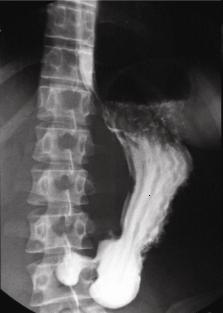

TOGD duodenum debout :

images en serie de D1, genus superieure , D2 , genus

inferieure , D3 et D4 . Angle de Treizt est en vue

arriere de angle de petit courbure . Bulbe est en

pleine de baryte et se voyait normalement |

Arcade duodenum et antrum :

Images TOGD avec compression de la region bulbaire . |

Estomac , antrum

, pylore et ---arcade

duodenum en profile . |